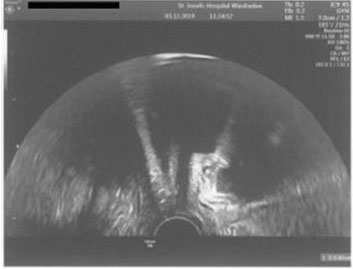

Case Report: We report the case of a 31-year-old female with a history of an umbilical hernia repair who presented with acute abdominal findings at 22 weeks gestation attributed to delayed infection of surgical mesh.